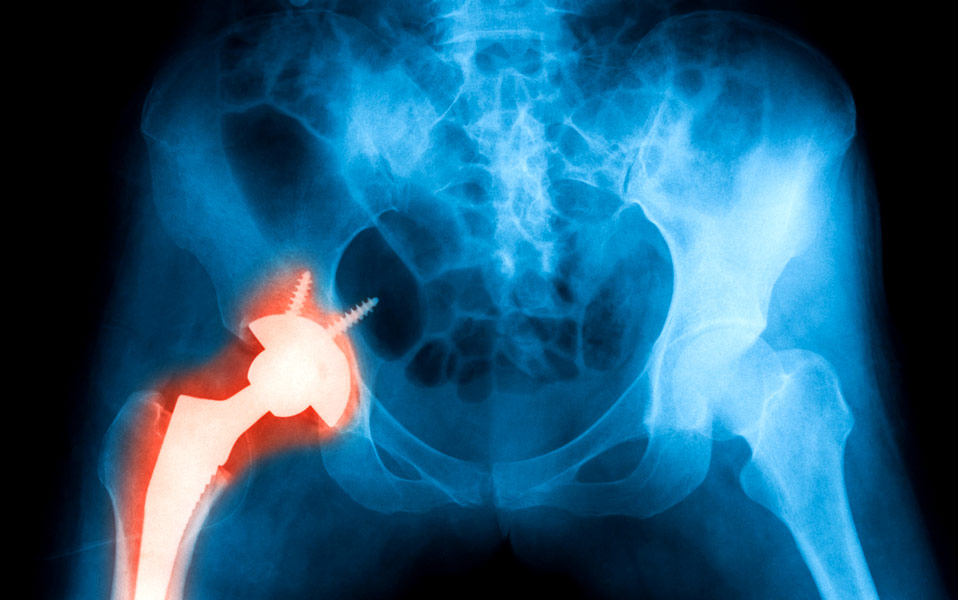

Αναθεώρηση της ολικής αρθροπλαστικής του ισχίου: Τώρα και με τεχνική ελάχιστης επεμβατικότητας ASI

Η ολική αρθροπλαστική ισχίου είναι μία από τις πιο επιτυχημένες χειρουργικές επεμβάσεις στην ορθοπαιδική. Παρόλα αυτά, ένας σημαντικός αριθμός ασθενών υποβάλλεται σε αναθεώρηση (δεύτερη επέμβαση/επανεπέμβαση/revision).